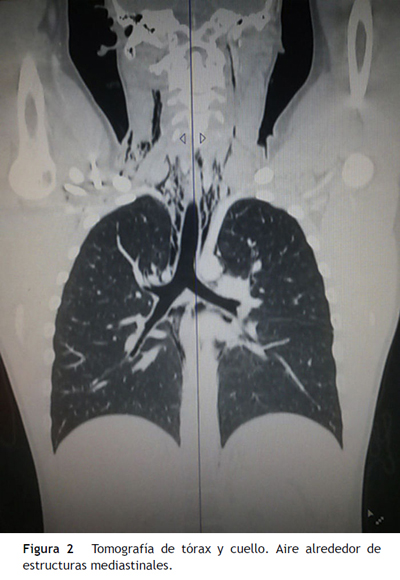

El ecocardiograma se encontró dentro de límites normales, descartándose la presencia de pericarditis, derrame pericárdico u otra patología cardiaca. La tomografía axial computarizada de cuello y tórax para descartar otras patologías pulmonares o mediastinales mostró presencia de aire rodeando las estructuras del mediastino, el cuello y escasas burbujas en algunos forámenes vertebrales y saco tecal, y enfisema subcutáneo a nivel cervical (fig. 2). Se inició manejo de soporte con analgesia, reposo y oxígeno suplementario. La evolución fue favorable, con control adecuado del dolor, y se le dio salida al paciente al quinto día de hospitalización. En un control a las 48 horas de salida se encontró resolución completa del dolor, y en la radiografía del tórax, ausencia de neumomediastino.

La tomografía de tórax es más específica y detecta lesiones más pequeñas, pero se debe reservar para el estudio de una patología pulmonar subyacente y no es una herramienta de uso rutinario7. El esofagograma, la esofagoscopia y la broncoscopia solo están indicados en aquellos pacientes en los que se sospeche un origen secundario14, especialmente en los menores de 6 años de edad.